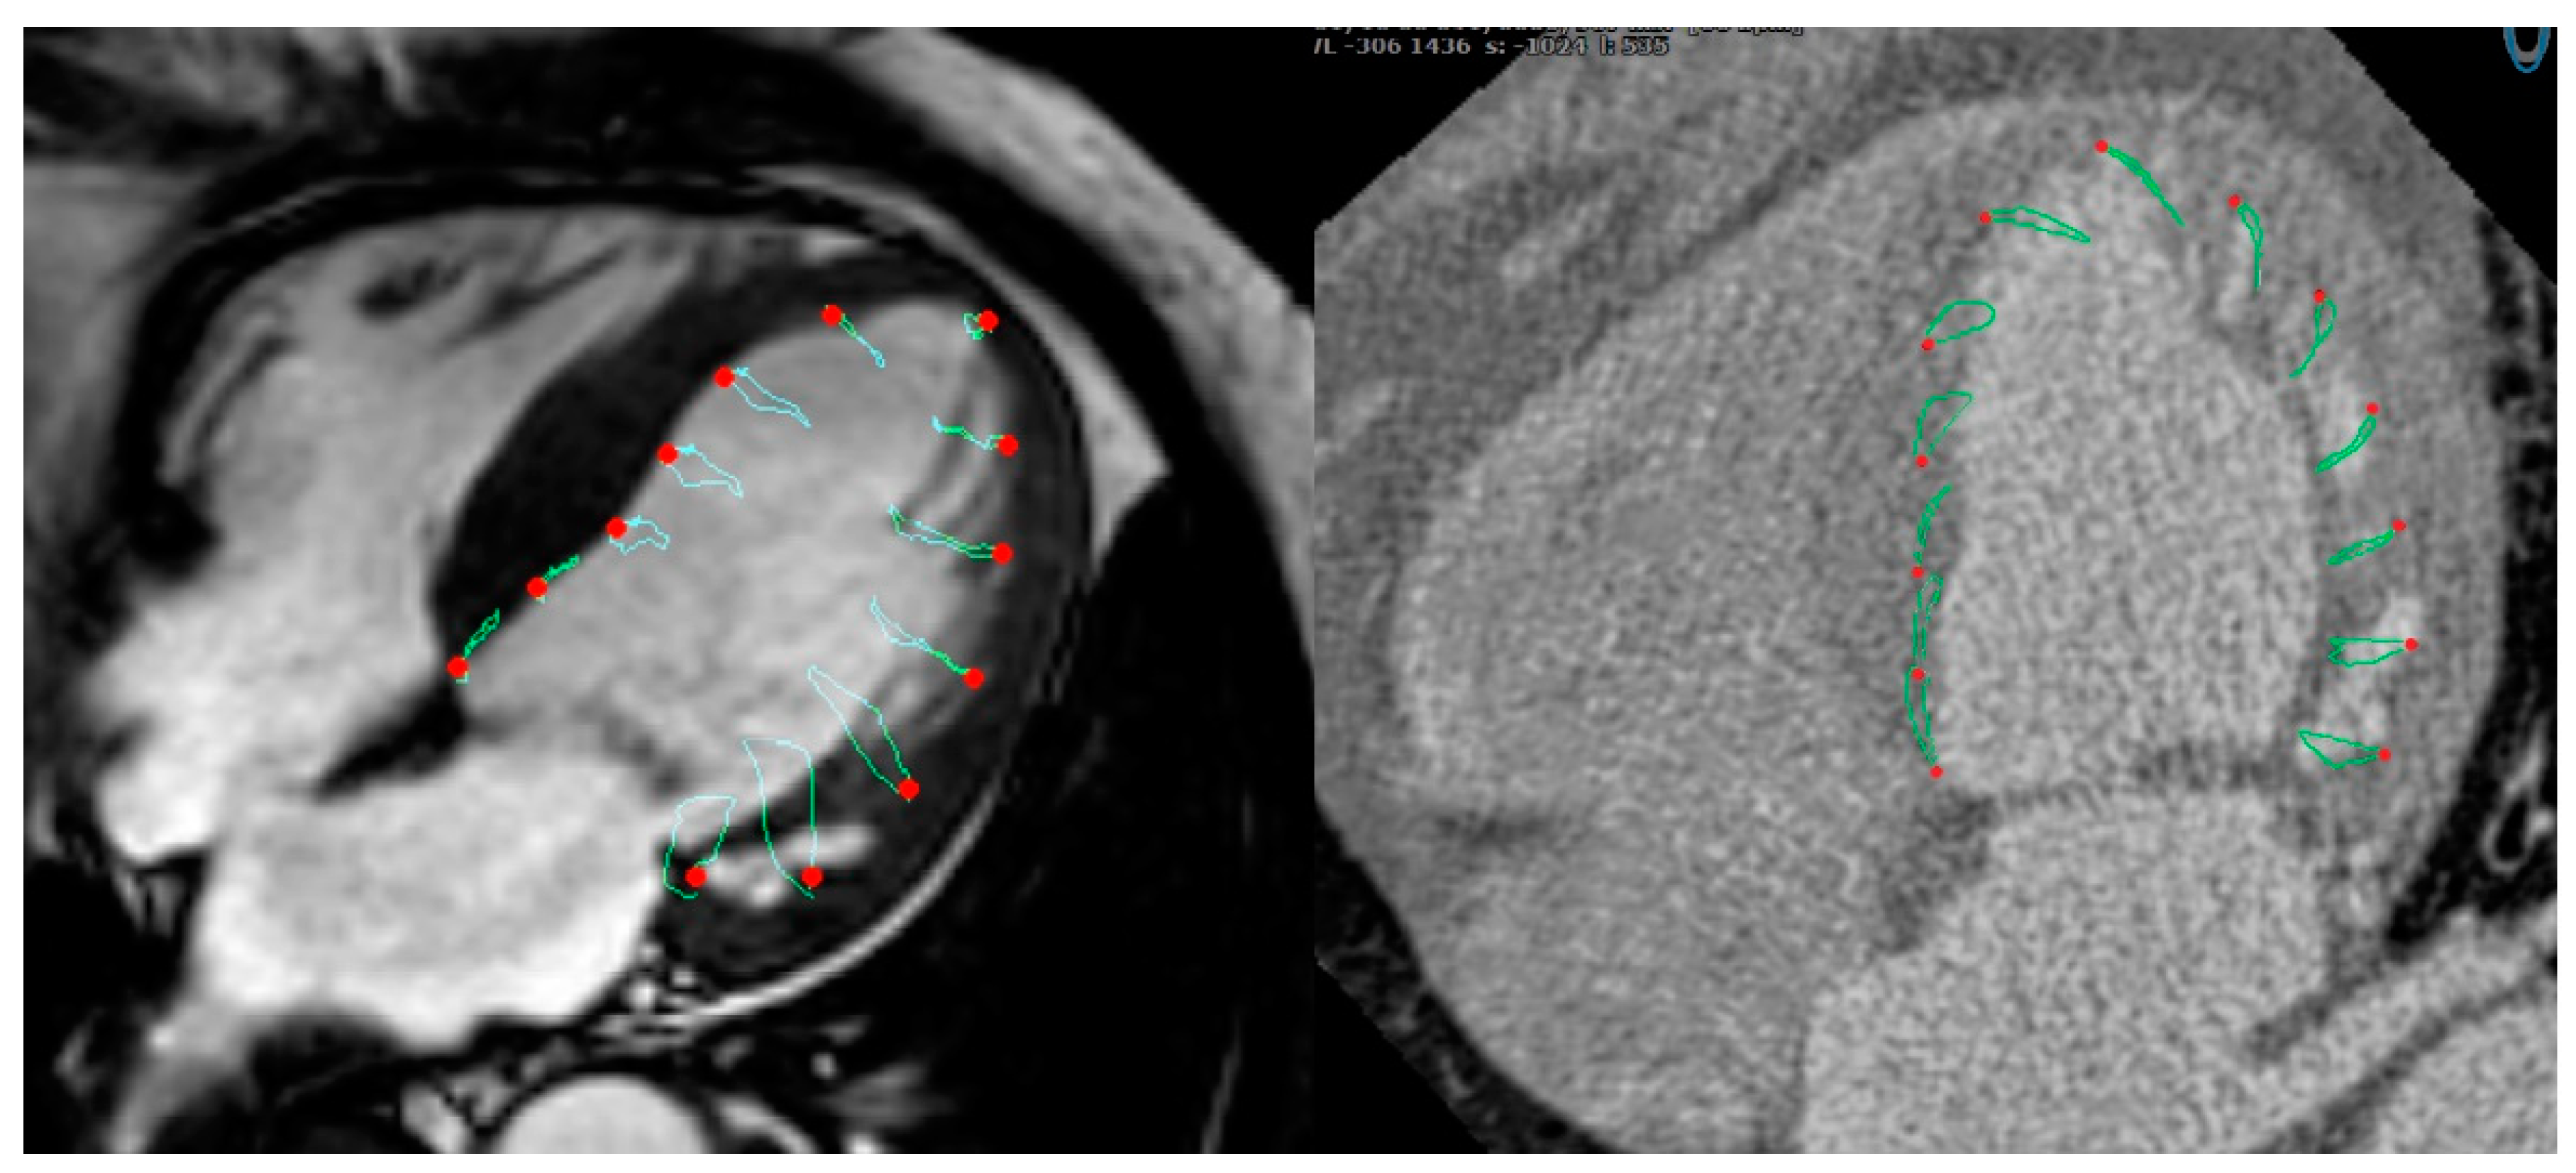

2.4. Cardiac CT Data Analysis

2.5. CMR Data Analysis